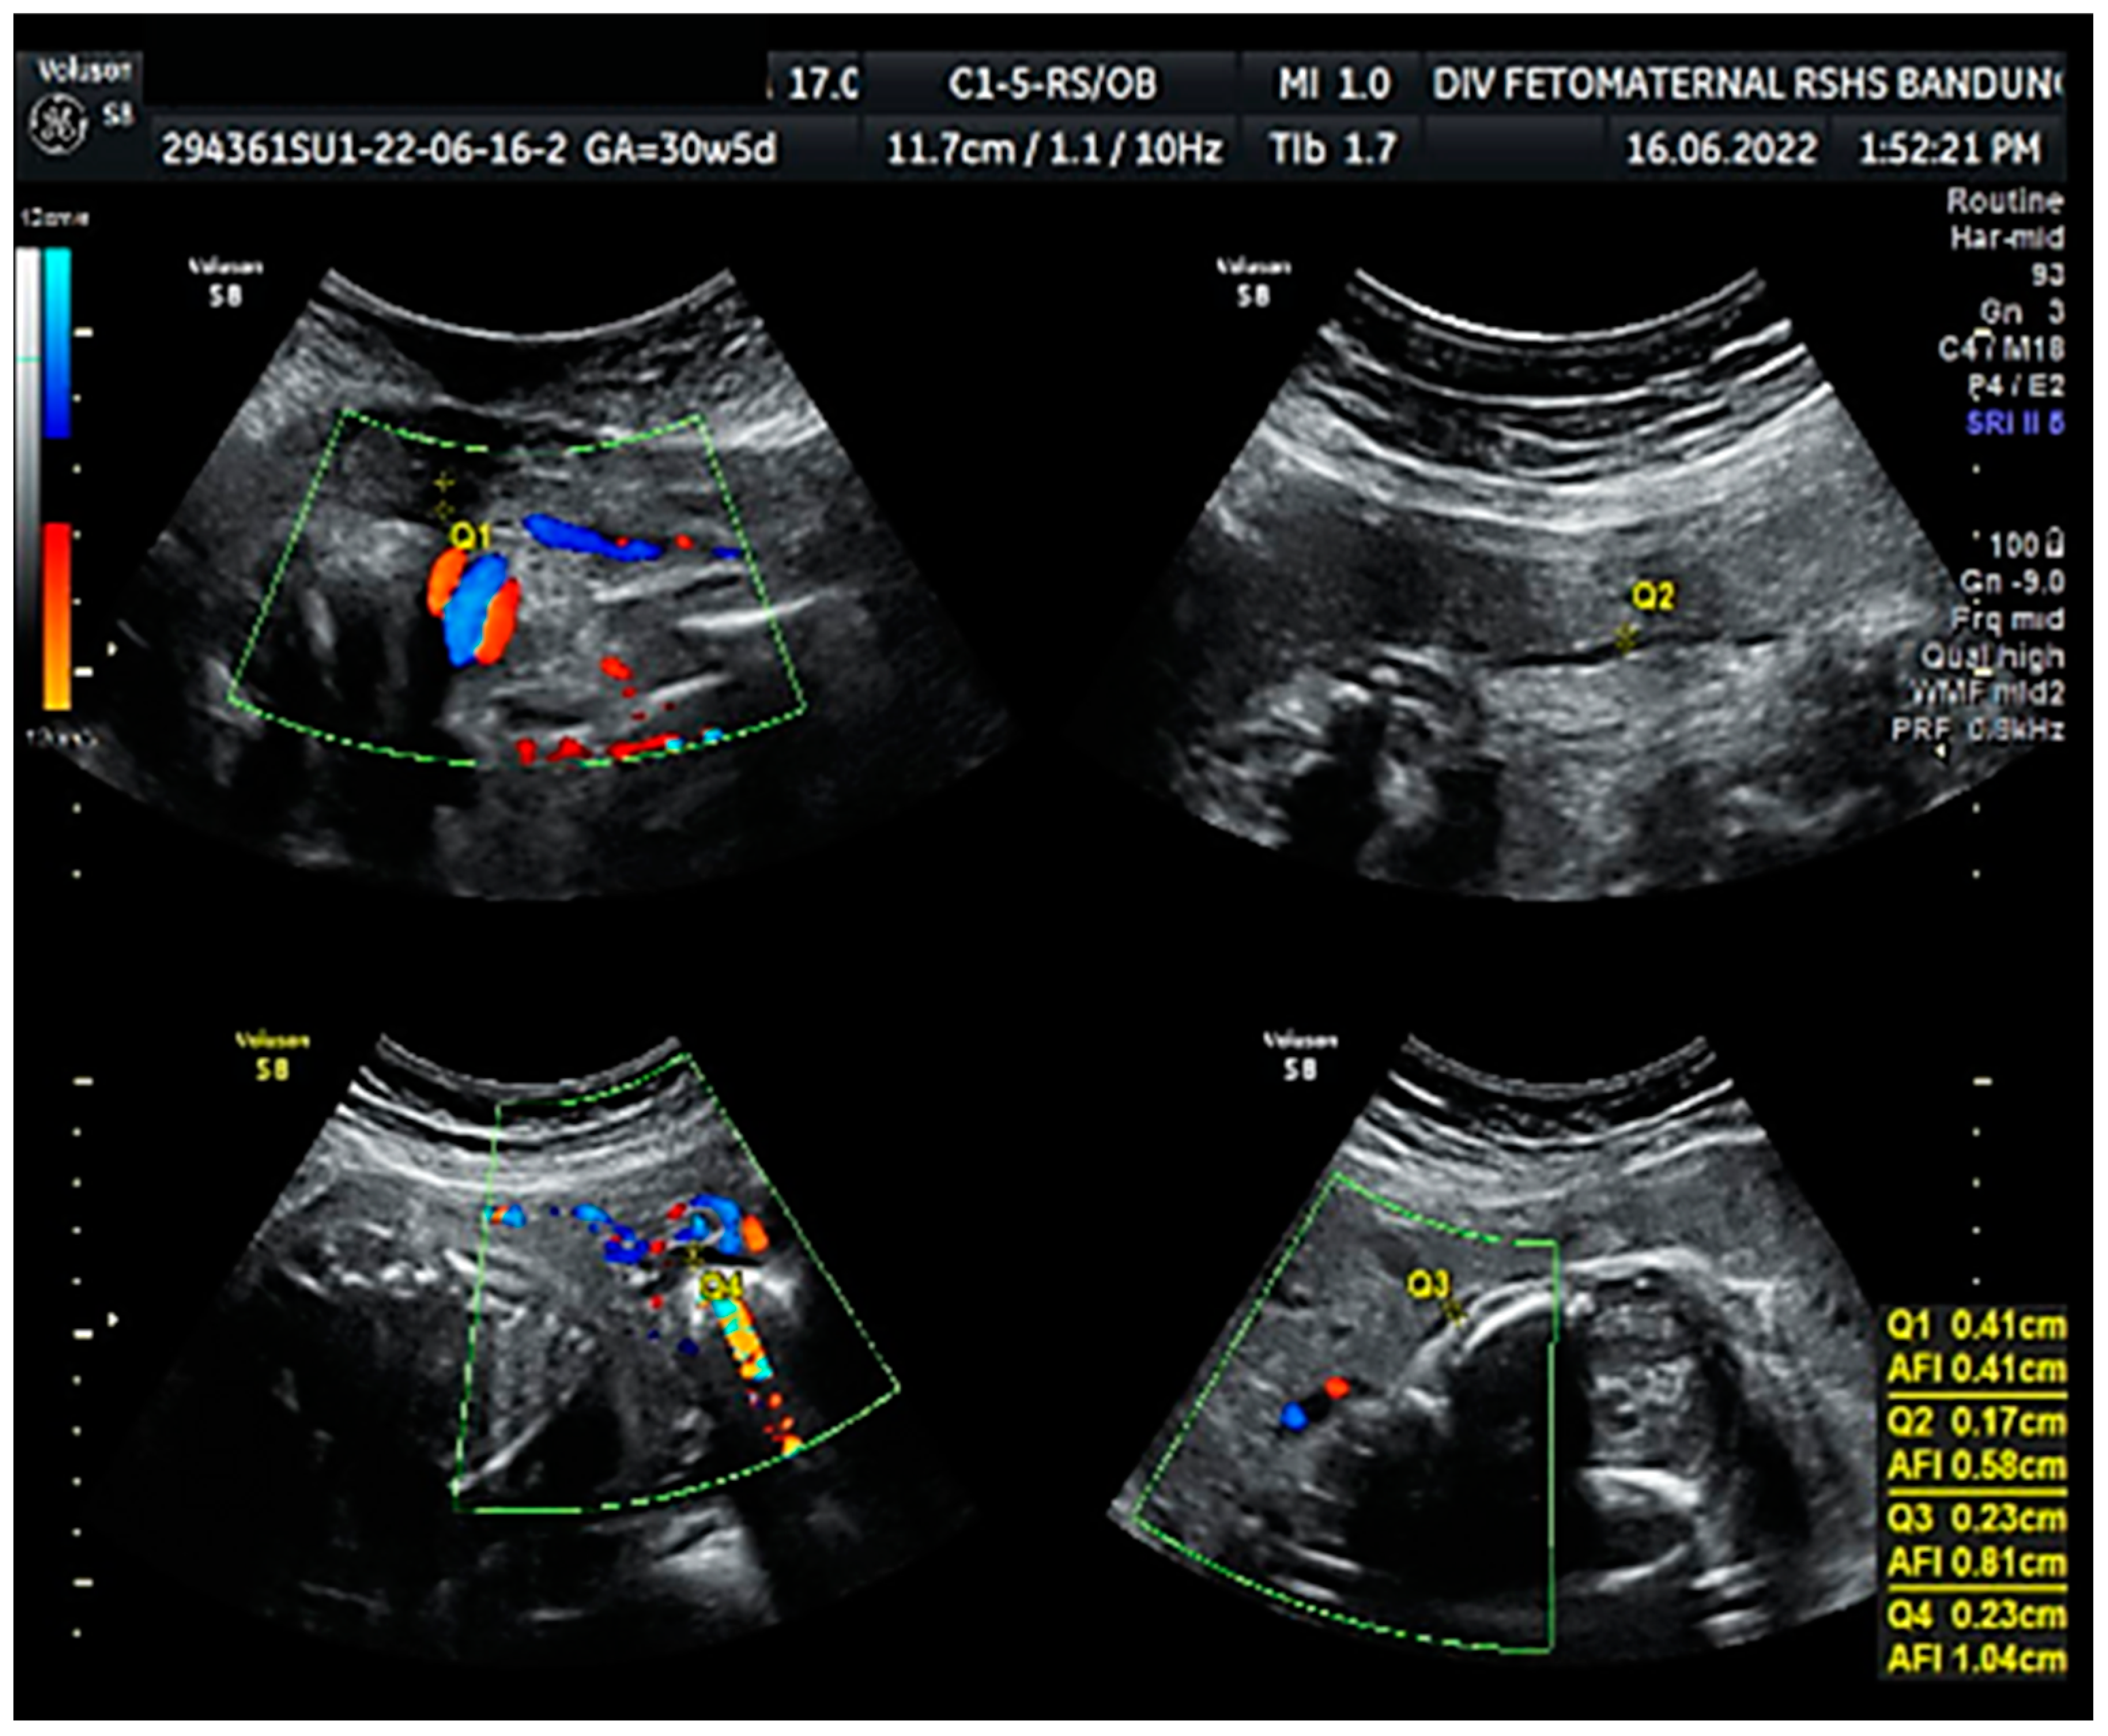

Color Doppler examination of the MCA revealed a peak systolic velocity of 42.33 cm/s, which is 1.045 times the median (the normal range is 40.5 cm/s for this gestational age), with persistent reversed end diastolic flow (Figure 2). The umbilical artery pulsatility index (PI) was 0.99, and RI was 0.63, with an S/D ratio of 2.71. There was notching on the right uterine artery, with a PI of 2.11. Notching was also found on the left uterine artery, with a PI of 1.58 (Figure 3). Laboratory results were within a normal range.

Figure 2. Reversed end diastolic flow in the middle cerebral artery.